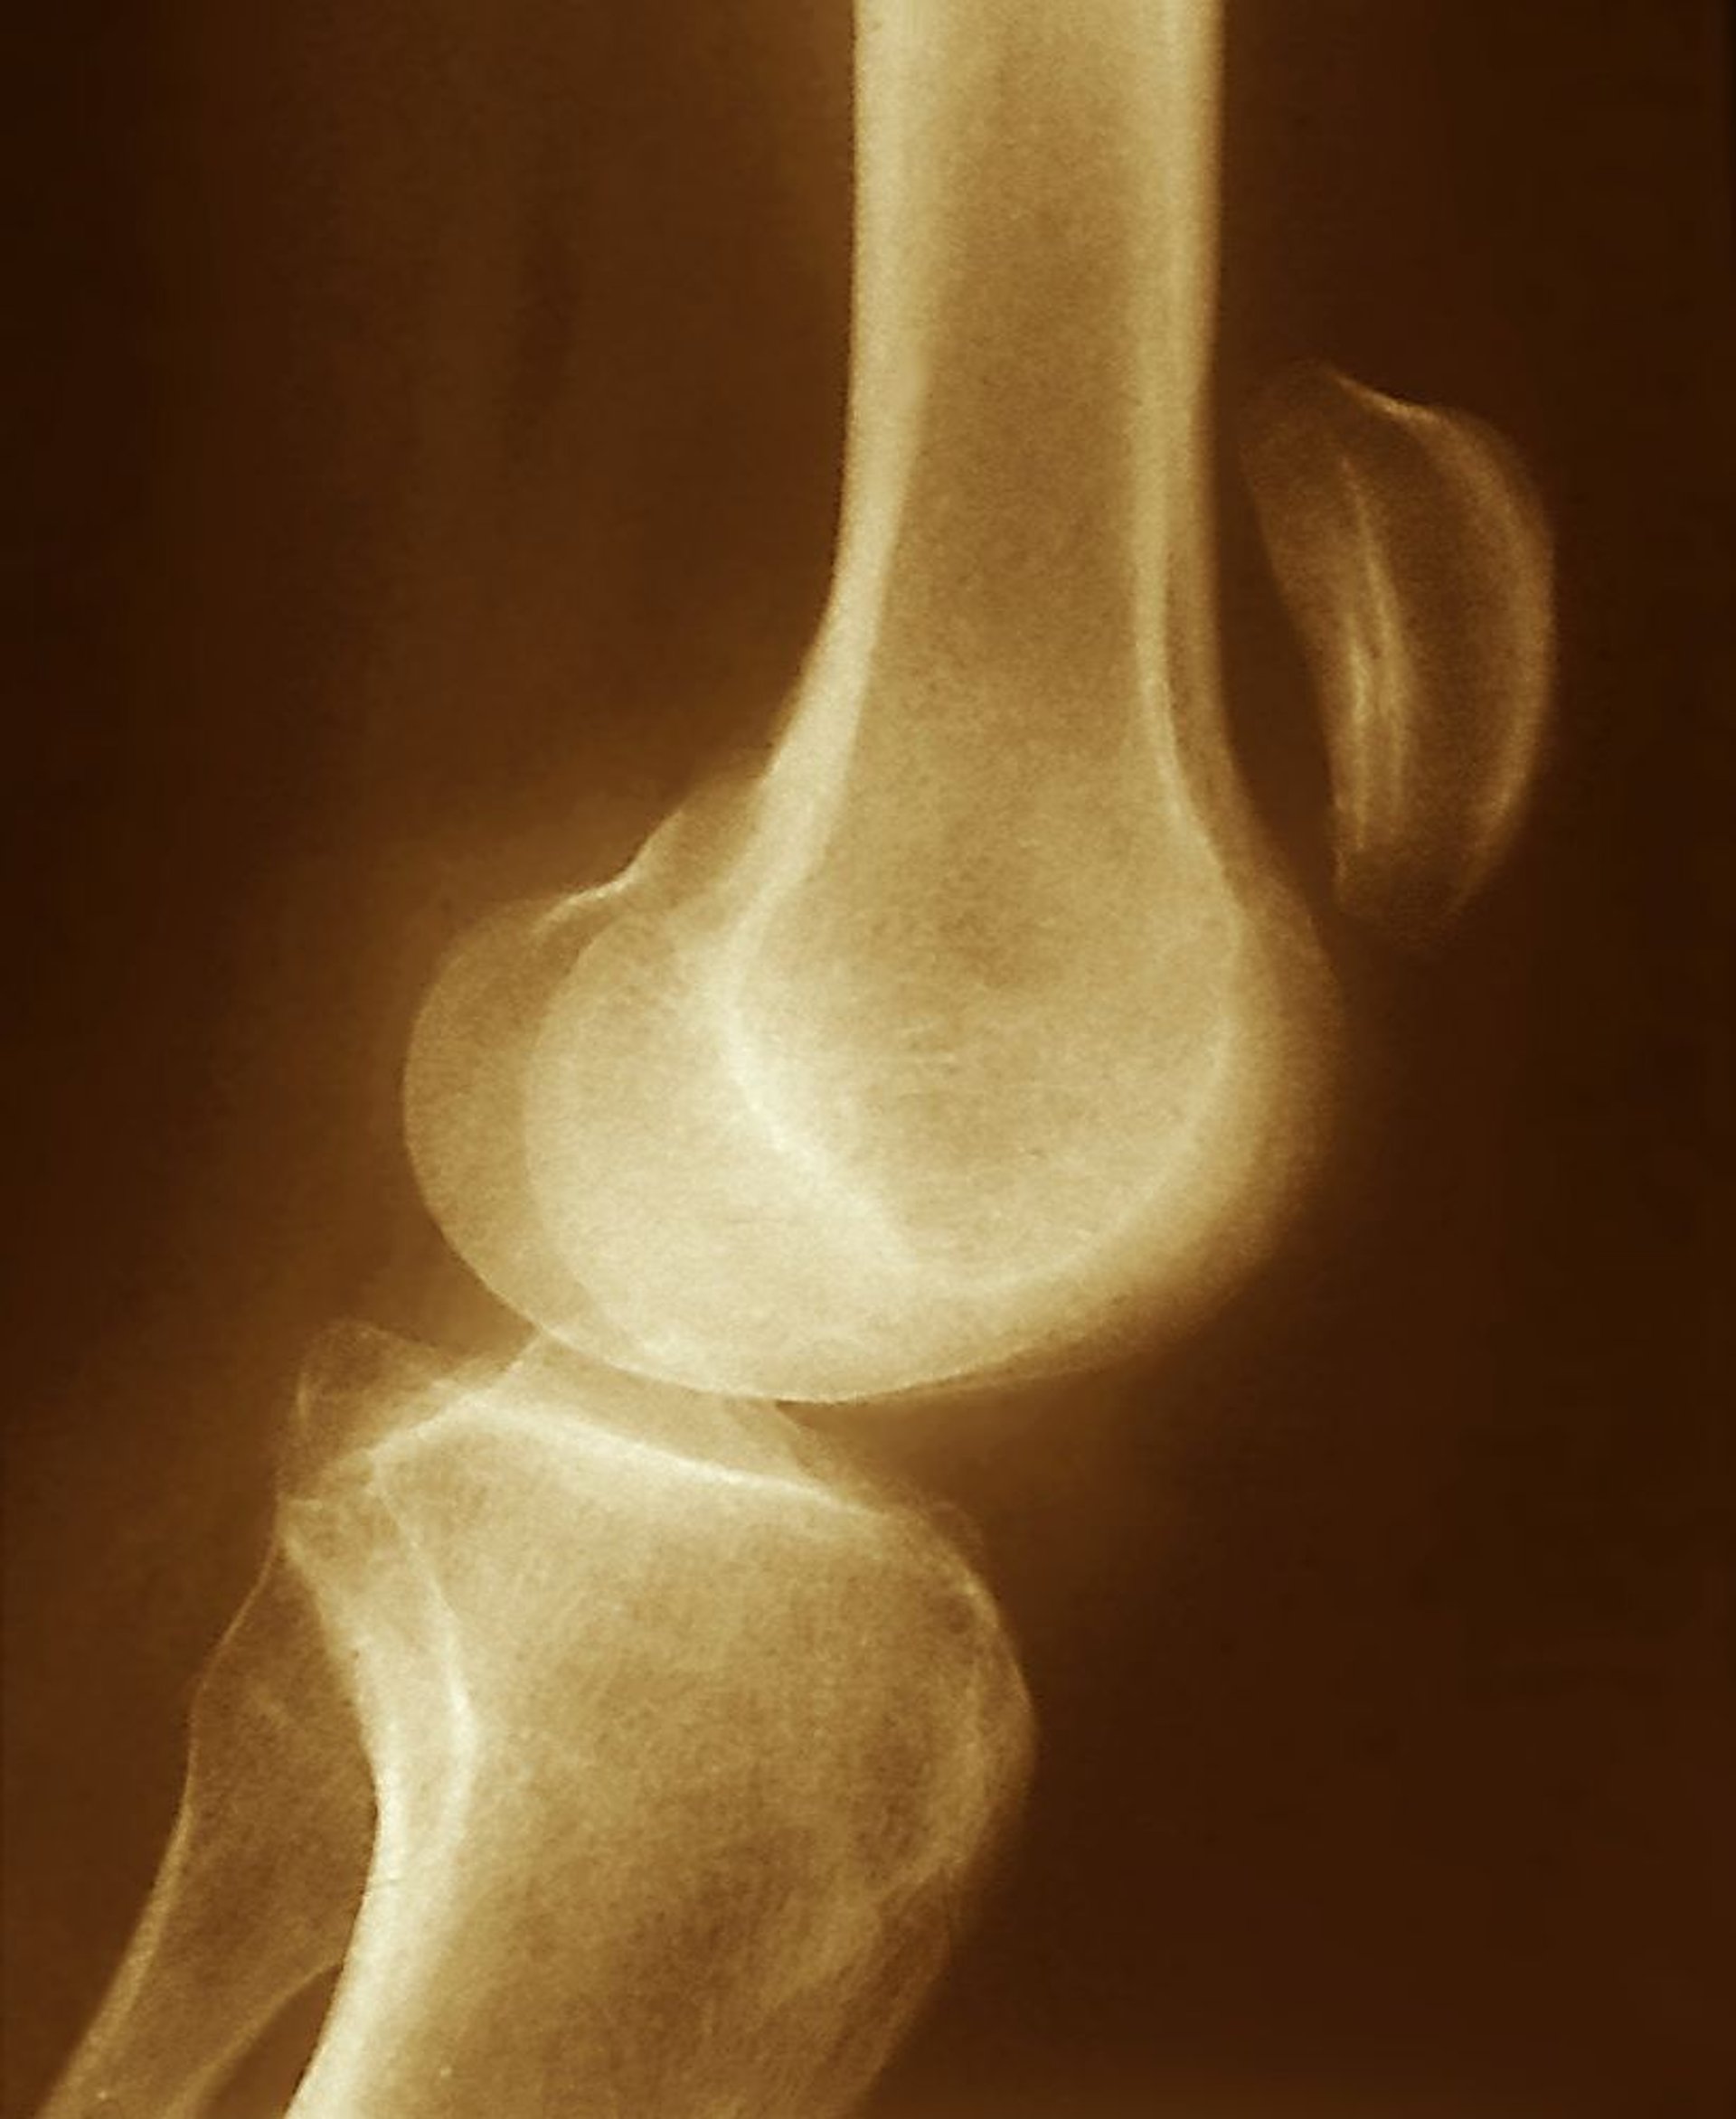

Rách gân xương bánh chè

Thấy xương bánh chè dịch chuyển lên trên trên phim chụp X-quang này (phía trên khớp gối) gợi ý một vết rách của gân xương bánh chè, cùng với co cơ tứ đầu đùi không trái ngược.

ZEPHYR/THƯ VIỆN HÌNH ẢNH KHOA HỌC